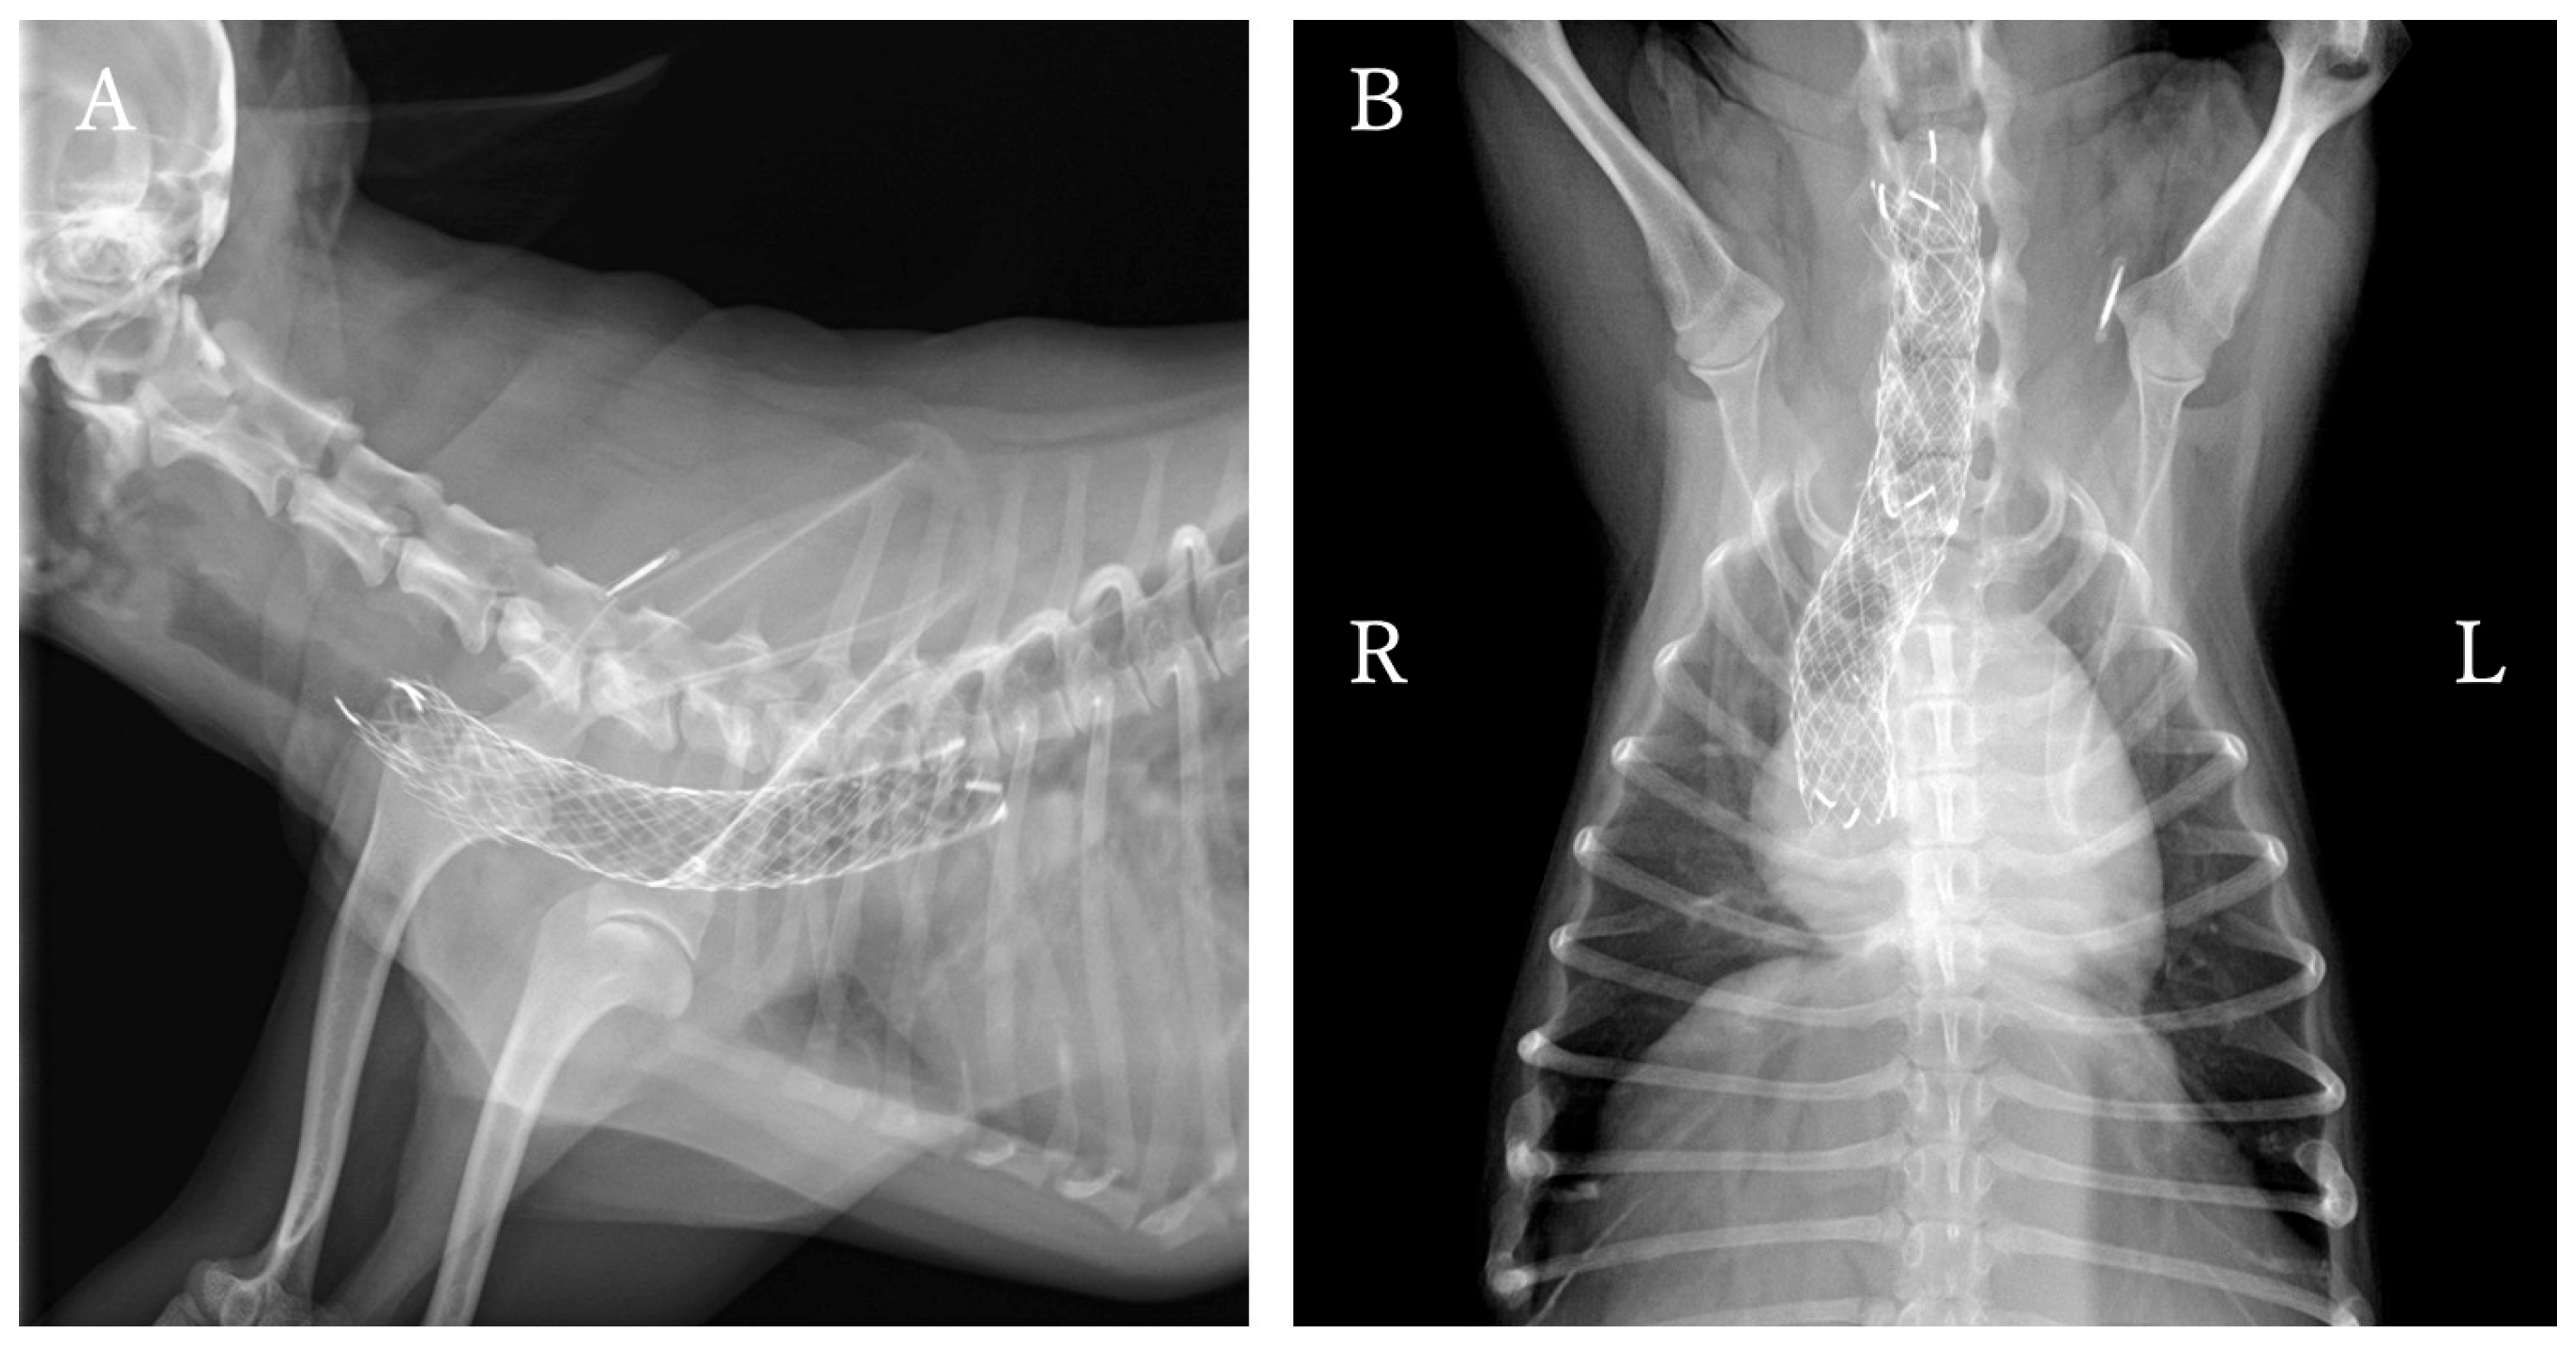

At one year and one month after ELS placement, the patient was re-presented to the hospital with increased coughing frequency and worsening respiratory sounds. Physical examination revealed inspiratory labored breathing and coughing. Radiography and fluoroscopy revealed that the stent had fractured at the tracheal collapse site identified at the initial presented (Figure 4A,B). Additionally, tracheal collapse was observed at the cranial end of the stent. Treatment options considered included placing a new tracheal stent or placing a PLLP. The owner requested PLLP placement, which was performed the following day.

Bronchoscopy revealed that the tracheal stent was entirely covered by granulation tissue, obscuring its structure. At the site of fractured, a portion of the stent protruded into the tracheal lumen (Figure 4D). Additionally, the ventral aspect of the tracheal cartilage was found to be invaginated toward the lumen, resulting in flattening of the tracheal lumen.

A ventral midline approach to the cervical trachea was performed. Dissection was performed while preserving the tracheal blood vessels as much as possible, and the recurrent laryngeal nerves were identified under direct visualization. The fractured area of the stent showed deformation of the cartilage, which had collapsed into the tracheal lumen and flattened (Figure 4C).

To avoid injury to the recurrent laryngeal nerve, umbilical cord tape was applied to the cranial and caudal sides of the planned PLLP placement site, allowing traction only on the trachea. The PLLP was positioned to cover the damaged area and the cephalic end of the trachea. To prioritize repair of the ventral deformation, the ring opening was oriented dorsally.

A 4-0 Polypropylene Monofilament suture (PROLENE 17 mm 3/8c taperpoint; Johnson & Johnson, Tokyo, Japan) was used for fixation. The ligature was performed by threading the suture through the endotracheal stent as well, thereby pulling the damaged stent while reshaping the tracheal contour. On the ventral side, 3–4 ligations were placed at the fractured site and 2–3 at the non-lesional site. Additionally, one fixation/support suture was added to each ventrolateral side to enhance operability. Pulling the support suture mildly rotated the trachea, allowing ligation of the dorsal loop and reshaping the trachea into a circular form (Figure 4G).

After all sutures were placed, sterile saline was instilled into the trachea to confirm no air leakage from the suture sites. Bronchoscopy revealed the stent protruding into the tracheal lumen had disappeared, and the previously flattened tracheal lumen had clearly improved to a circular shape (Figure 4H).

Figure 4. Pre- and post-placement findings of the PLLP used to manage tracheal stent fracture. (AD) Pre-PLLP placement images. (EH) Post-PLLP placement images. (A) Cervicothoracic radiographs in the right lateral view showing complete fracture of the endoluminal tracheal stent, with associated tracheal narrowing at the fracture site and cranial to the stent. (B) Cervicothoracic radiographs in the ventrodorsal view. (C) Cervical view demonstrating protrusion of a fractured stent segment into the tracheal lumen. Ventral tracheal cartilage invagination was also present, resulting in luminal flattening. (D) Bronchoscopy showing marked deformation of the tracheal lumen at the fracture site. (E) Cervicothoracic radiographs in the right lateral view showing successful reshaping and stabilization of the intraluminal stent. (F) Cervicothoracic radiographs in the ventrodorsal view. (G) Cervical view demonstrating restoration of a near-normal tracheal contour. (H) Bronchoscopy confirming improvement in tracheal luminal shape.